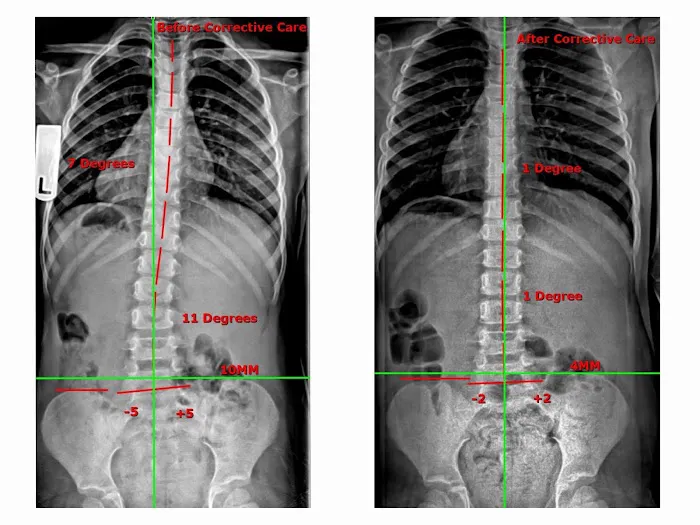

Align Chiropractic offers a comprehensive suite of services designed to address a variety of health issues, with a strong emphasis on corrective and long-term care. The practice uses a combination of time-tested chiropractic techniques and modern technology to provide effective treatment. Before beginning any treatment, the team takes the time to conduct a thorough examination, which often includes x-rays, to get a clear picture of a patient's unique needs and the root cause of their discomfort. This detailed diagnostic process allows them to create a truly personalized treatment plan. The services are not just for those in pain; they are also beneficial for individuals seeking to improve their posture, athletic performance, or general wellness. The focus on educating patients and providing them with tools for at-home care ensures that the benefits of the treatment extend far beyond the office visits.

May 19, 2025 · Christine OI went to Align after going to a chiropractor, massage therapist, physical therapist, and doing different stretches and yoga. I could not put my socks on in the morning. That was the litmus test. After Xrays there was misalignment from the neck down to the lower back. More significantly I had three bulged discs due to bad posture, fractured coccyx, sitting down for long periods. 6 months later after intense home trainings and multiple sessions a week, I could move freely. 2 years later I can go back to squatting and deadlifting my weight and more. To this day I still do the home exercises with the equipment that was provided.